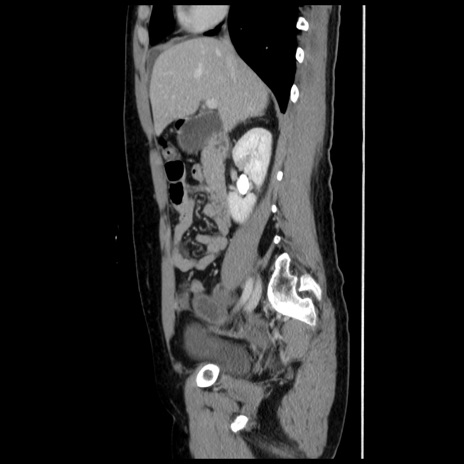

冠状断像

【症例】 50歳代女性

【主訴】 腹痛

【現病歴】前日生レバーを食べた。今朝に排便あり。 昼前に突然発症の腹痛を生じ、当院救急外来を受診した。

【既往歴】 子宮筋腫にてで子宮全摘後

【身体所見】 意識清明、腹部:平坦、軟、下腹部やや左を中心に圧痛・反跳痛あり、筋性防御あり

【データ】WBC 7800、CRP 0.07